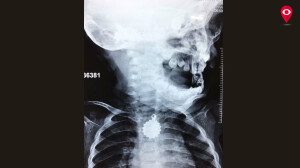

वडील खूप घाबरले. त्यांनी तिला कूपर रुग्णालयात दाखल केले. तिच्या अन्ननलिकेत लॉकेट अडकल्याचे डॉक्टरांनी सांगितले. डॉ. शशिकांत मशळ यांनी तत्काळ रुकय्याला ऑपरेशन थिएटरमध्ये नेले आणि एन्डोक्सोपीने तिच्या घशातील लॉकेट बाहेर काढले.

“ मंगळवारी रात्री रुकय्याला तिचे कुटुंबीय खूप घाबरलेल्या अवस्थेत रुग्णालयात घेऊन आले. त्यावेळी आम्ही तिला दाखल करुन घेतलं, तेव्हा कळलं की लॉकेट तिच्या घशाच्या अन्ननलिकेत फसलं आहे. लॉकेटचा बाह्यभाग धारधार असल्याने अगदी सावधपणे, अलगद आम्हाला एन्डोस्कोपी करावी लागली. नाहीतर तिच्या अन्ननलिकेला इजा झाली असती. पण, तिच्यावर आम्ही जेव्हा एन्डोस्कोपी केली तेव्हा अजिबात इजा होऊ न देता ते लॉकेट बाहेर काढण्यात आम्हाला यश आलं. अशावेळी पालकांनीही लहान मुलं तोंडात काही घालणार नाहीत याची काळजी घेतली पाहिजे. आता रुकय्याची प्रकृती उत्तम आहे. गुरुवारी दुपारी तिला डिस्चार्ज देण्यात आला आहे. ”

डॉ.शशिकांत मशळ, कान-नाक-घसा विभाग प्रमुख, कुपर रुग्णालय